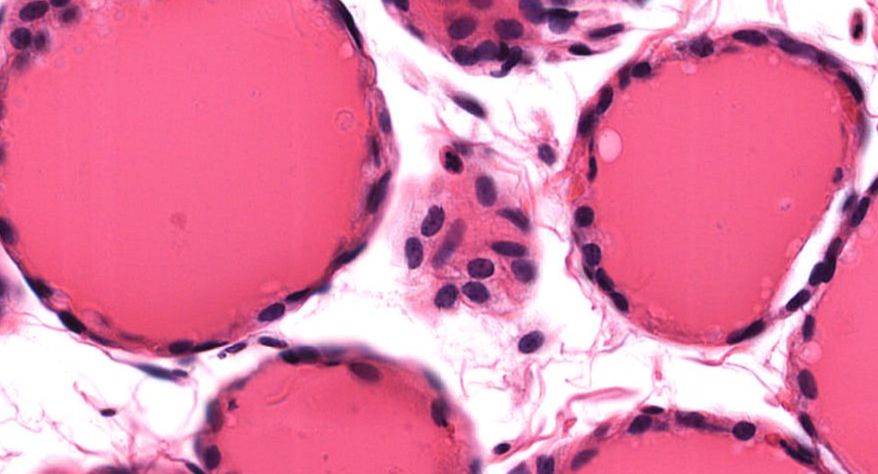

低倍镜观察:1. 被膜:由薄层结缔组织组成。2. 实质:由许多大小不等的滤泡构成。滤泡壁是单层立方上皮细胞,滤泡腔内充满粉红色匀质胶状物,滤泡之间的结缔组织内有丰富的血管。高倍镜观察:1. 滤泡:滤泡壁的单层滤泡上皮细胞一般呈低柱状或立方状,胞质着浅色,细胞核呈圆形。滤泡腔内充满了粉红色匀质胶质。2. 滤泡旁细胞:体积较大,呈圆形或椭圆形;细胞核较大,呈圆形,着色较浅,细胞质染色也较浅。细胞或嵌在滤泡壁上或成团分布于滤泡之间。3. 间质:由结缔组织组成。位于滤泡之间。其中含有丰富的毛细血管及三五成群的滤泡旁细胞。

2.滤泡

3.滤泡上皮细胞

4.胶质

5.滤泡旁细胞1

7.滤泡旁细胞2